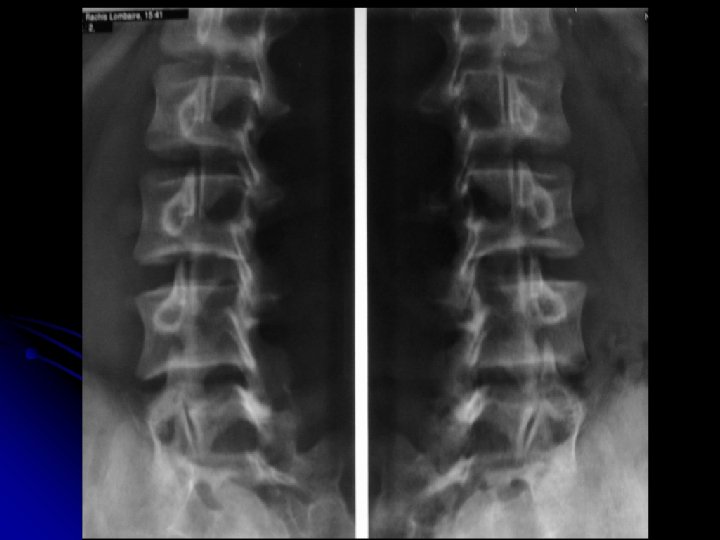

Rachis lombaire de face l Critères de réussite : l En haut : T 11 -T 12 l En bas: la symphyse pubienne et une partie des coxofémorales l Disques L 1 -L 2 à L 4 -L 5: enfilés.

l Statique rachidienne, l Morphologie: l des corps vertébraux, l des arcs postérieurs, et l’espace inter-arcual l Hauteur des espaces intervertébraux l Bords externes des psoas l Anomalie transitionnelle

l Autres incidences: l Cliché centré sur L 5 -S 1 l Obliques l Dynamiques